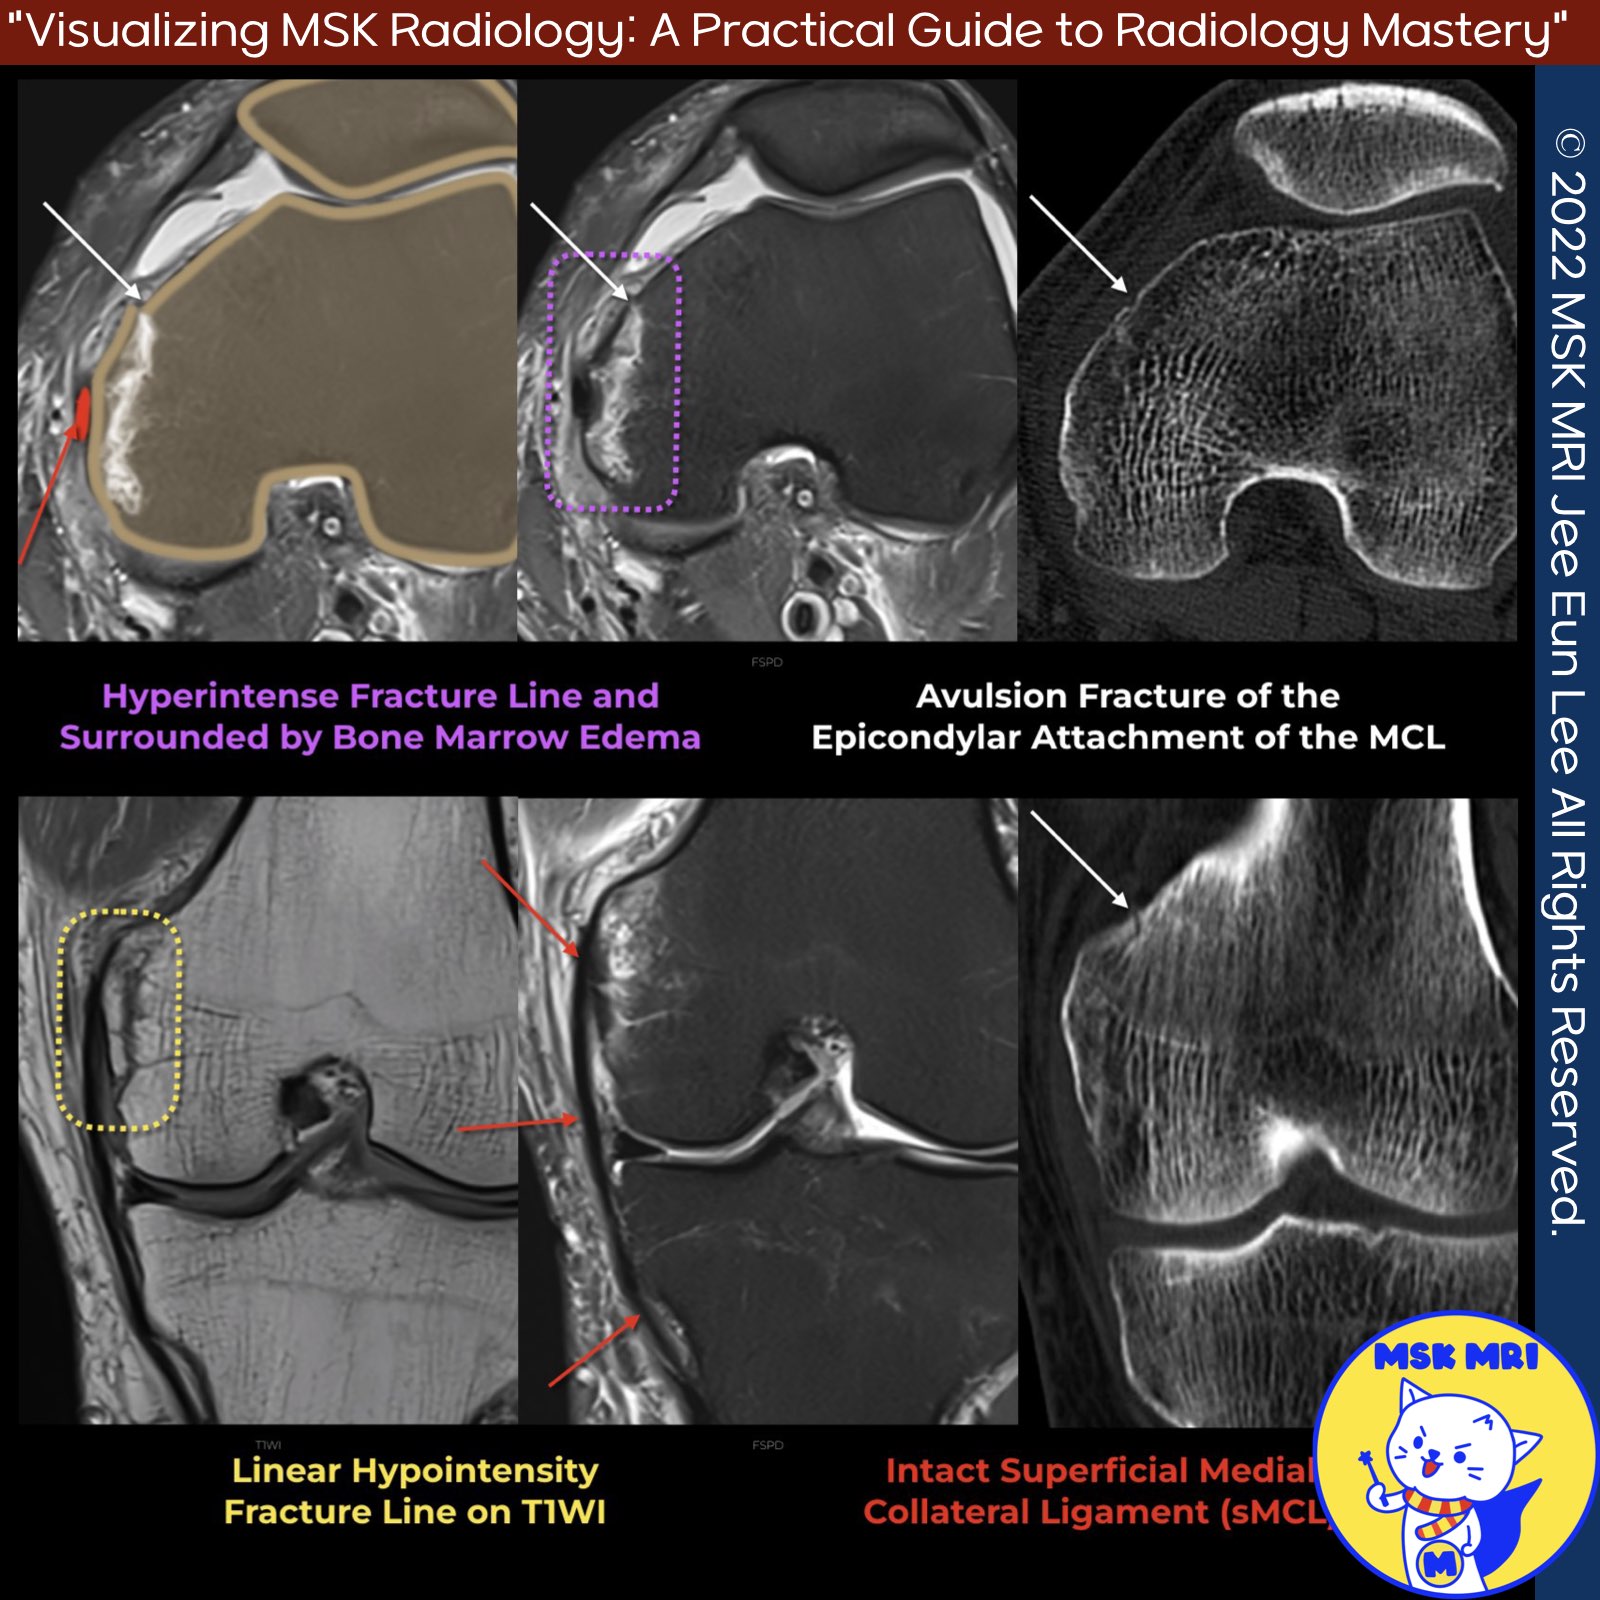

✅Avulsion fracture at the medial collateral ligament's epicondylar attachment.

✅ Key findings on imaging include:

- Avulsion fracture of the MCL visible, without displacement

- Continuity of the fracture fragment with the MCL on MRI

- Associated extracapsular hemorrhage appearing hyperintense

- Fracture line is hyperintense surrounded by bone marrow edema, making it less apparent on fat-suppressed images

- Fracture line appears as linear hypointensity on T1-weighted MRI

✅Note

It's important to assess for associated injuries like bone marrow edema, injury to posteromedial corner structures, deep MCL, medial meniscus, and cruciate ligaments which can accompany this type of avulsion fracture.